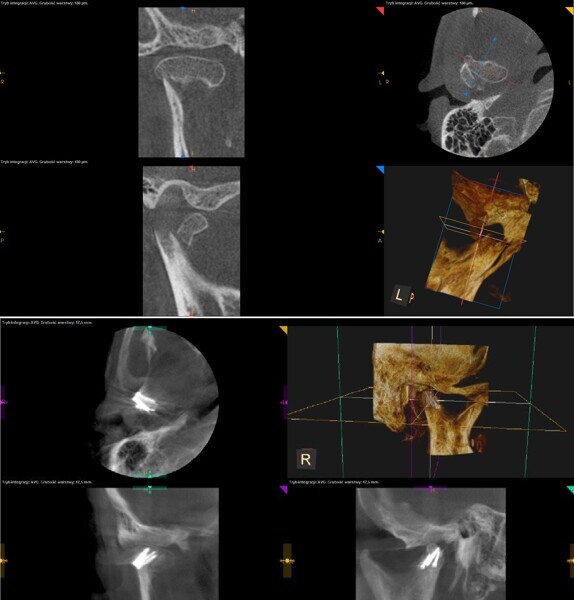

Ryc. 7_Tomografia stożkowa o zmiennym polu obrazowania – stan po urazie i po zaopatrzeniu chirurgicznym złamania.